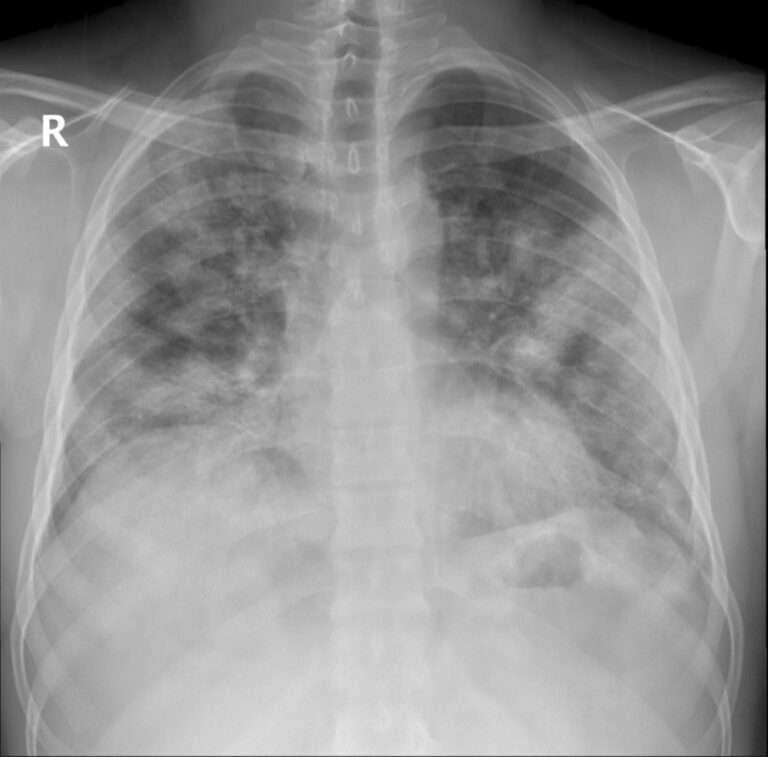

Doktorka Fatos Kozanlı, koja je pratila pacijenta, rekla je da bi pacijent mogao da bude prvi u svijetu zaražen takvim oblikom koronavirusa. On je patio od bolova u grudima kada je posjetio bolnicu i otkriveno je da ima tumor na desnom plućnom krilu, četiri centimetra širok. Nakon daljeg pregleda dijagnostifikovan mu je rak i zakazan je za operaciju.

Operacija je odložena kada je bio pozitivan na koronu. Kozanlı, koja je trebalo da ga operiše, uradila je posljednje snimke nakon što je pacijentov test na COVID-19 bio negativan. Tada je saznala da pacijent uopšte nema tumor.

“Imao je simptome vrlo, vrlo slične karcinomu pluća. Ali poslednje snimanje prije operacije pokazuje da je nestalo. Bili smo iznenađeni. Tumor ne može nestati sam od sebe. Da je patio od neke druge bolesti, ni to ne bi nestalo za tako kratko vrijeme. Naši nalazi pokazali su da je COVID-19 u potpunosti oponašao simptome raka pluća”, rekla je Kozanlı.